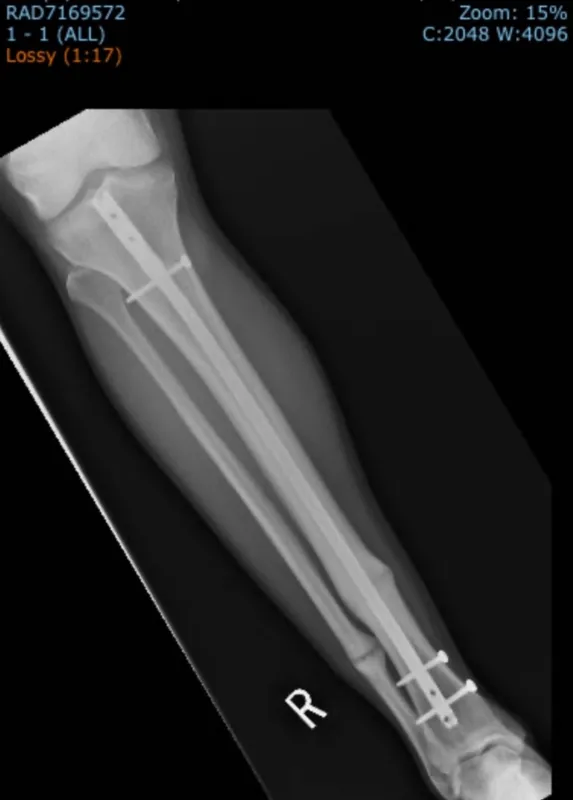

Later at University of Iowa Health Care, Phelps remembers talking to Matthew Karam, MD, an orthopedic surgeon who recommended same-day surgery to insert a titanium rod to stabilize the tibia. Both the tibia and the smaller fibula in Phelps’s right leg were broken.

Despite undergoing three surgeries in a year and a half — one to insert the rod on the tibia, another to fix the broken fibula that never healed, and the last to remove screws — Phelps was able to play football, at Iowa and then at Idaho State University during grad school. In February 2025, he completed the Mesa Marathon in Arizona.